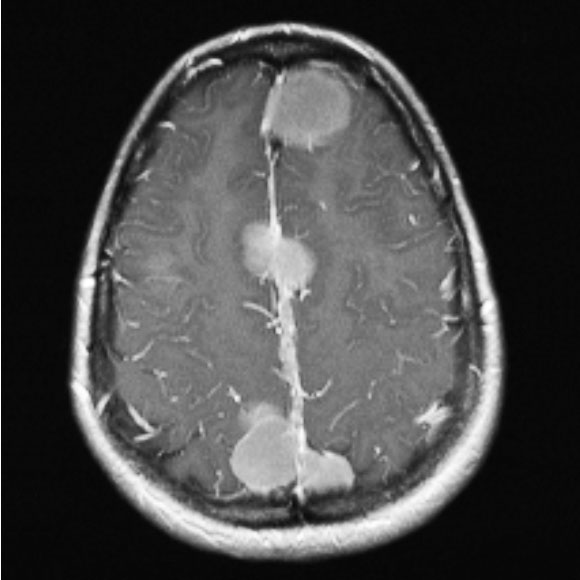

Опухоль 2 5 см

Опухоль 2 5 см 96 фото